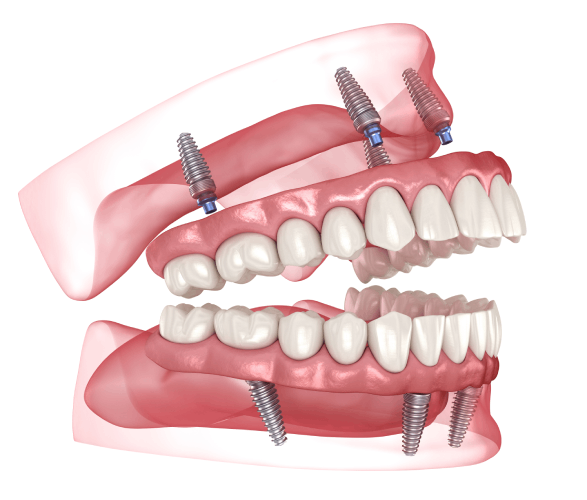

In this option, four to six implants are placed, depending on the shape and size of your jaw. These implants are joined with a custom-fitted bar, and the denture clips securely onto it. This solution offers more stability and reduced movement. The denture can be removed for cleaning and routine care.

Screw Retained Denture

This option places five or more implants into the jaw, supporting a denture that is screwed into place. It does not rest on the gums, which makes cleaning possible without removing the denture. While it requires more attention to hygiene and hand dexterity, it provides a fixed, durable solution that stays in place except during professional cleanings.